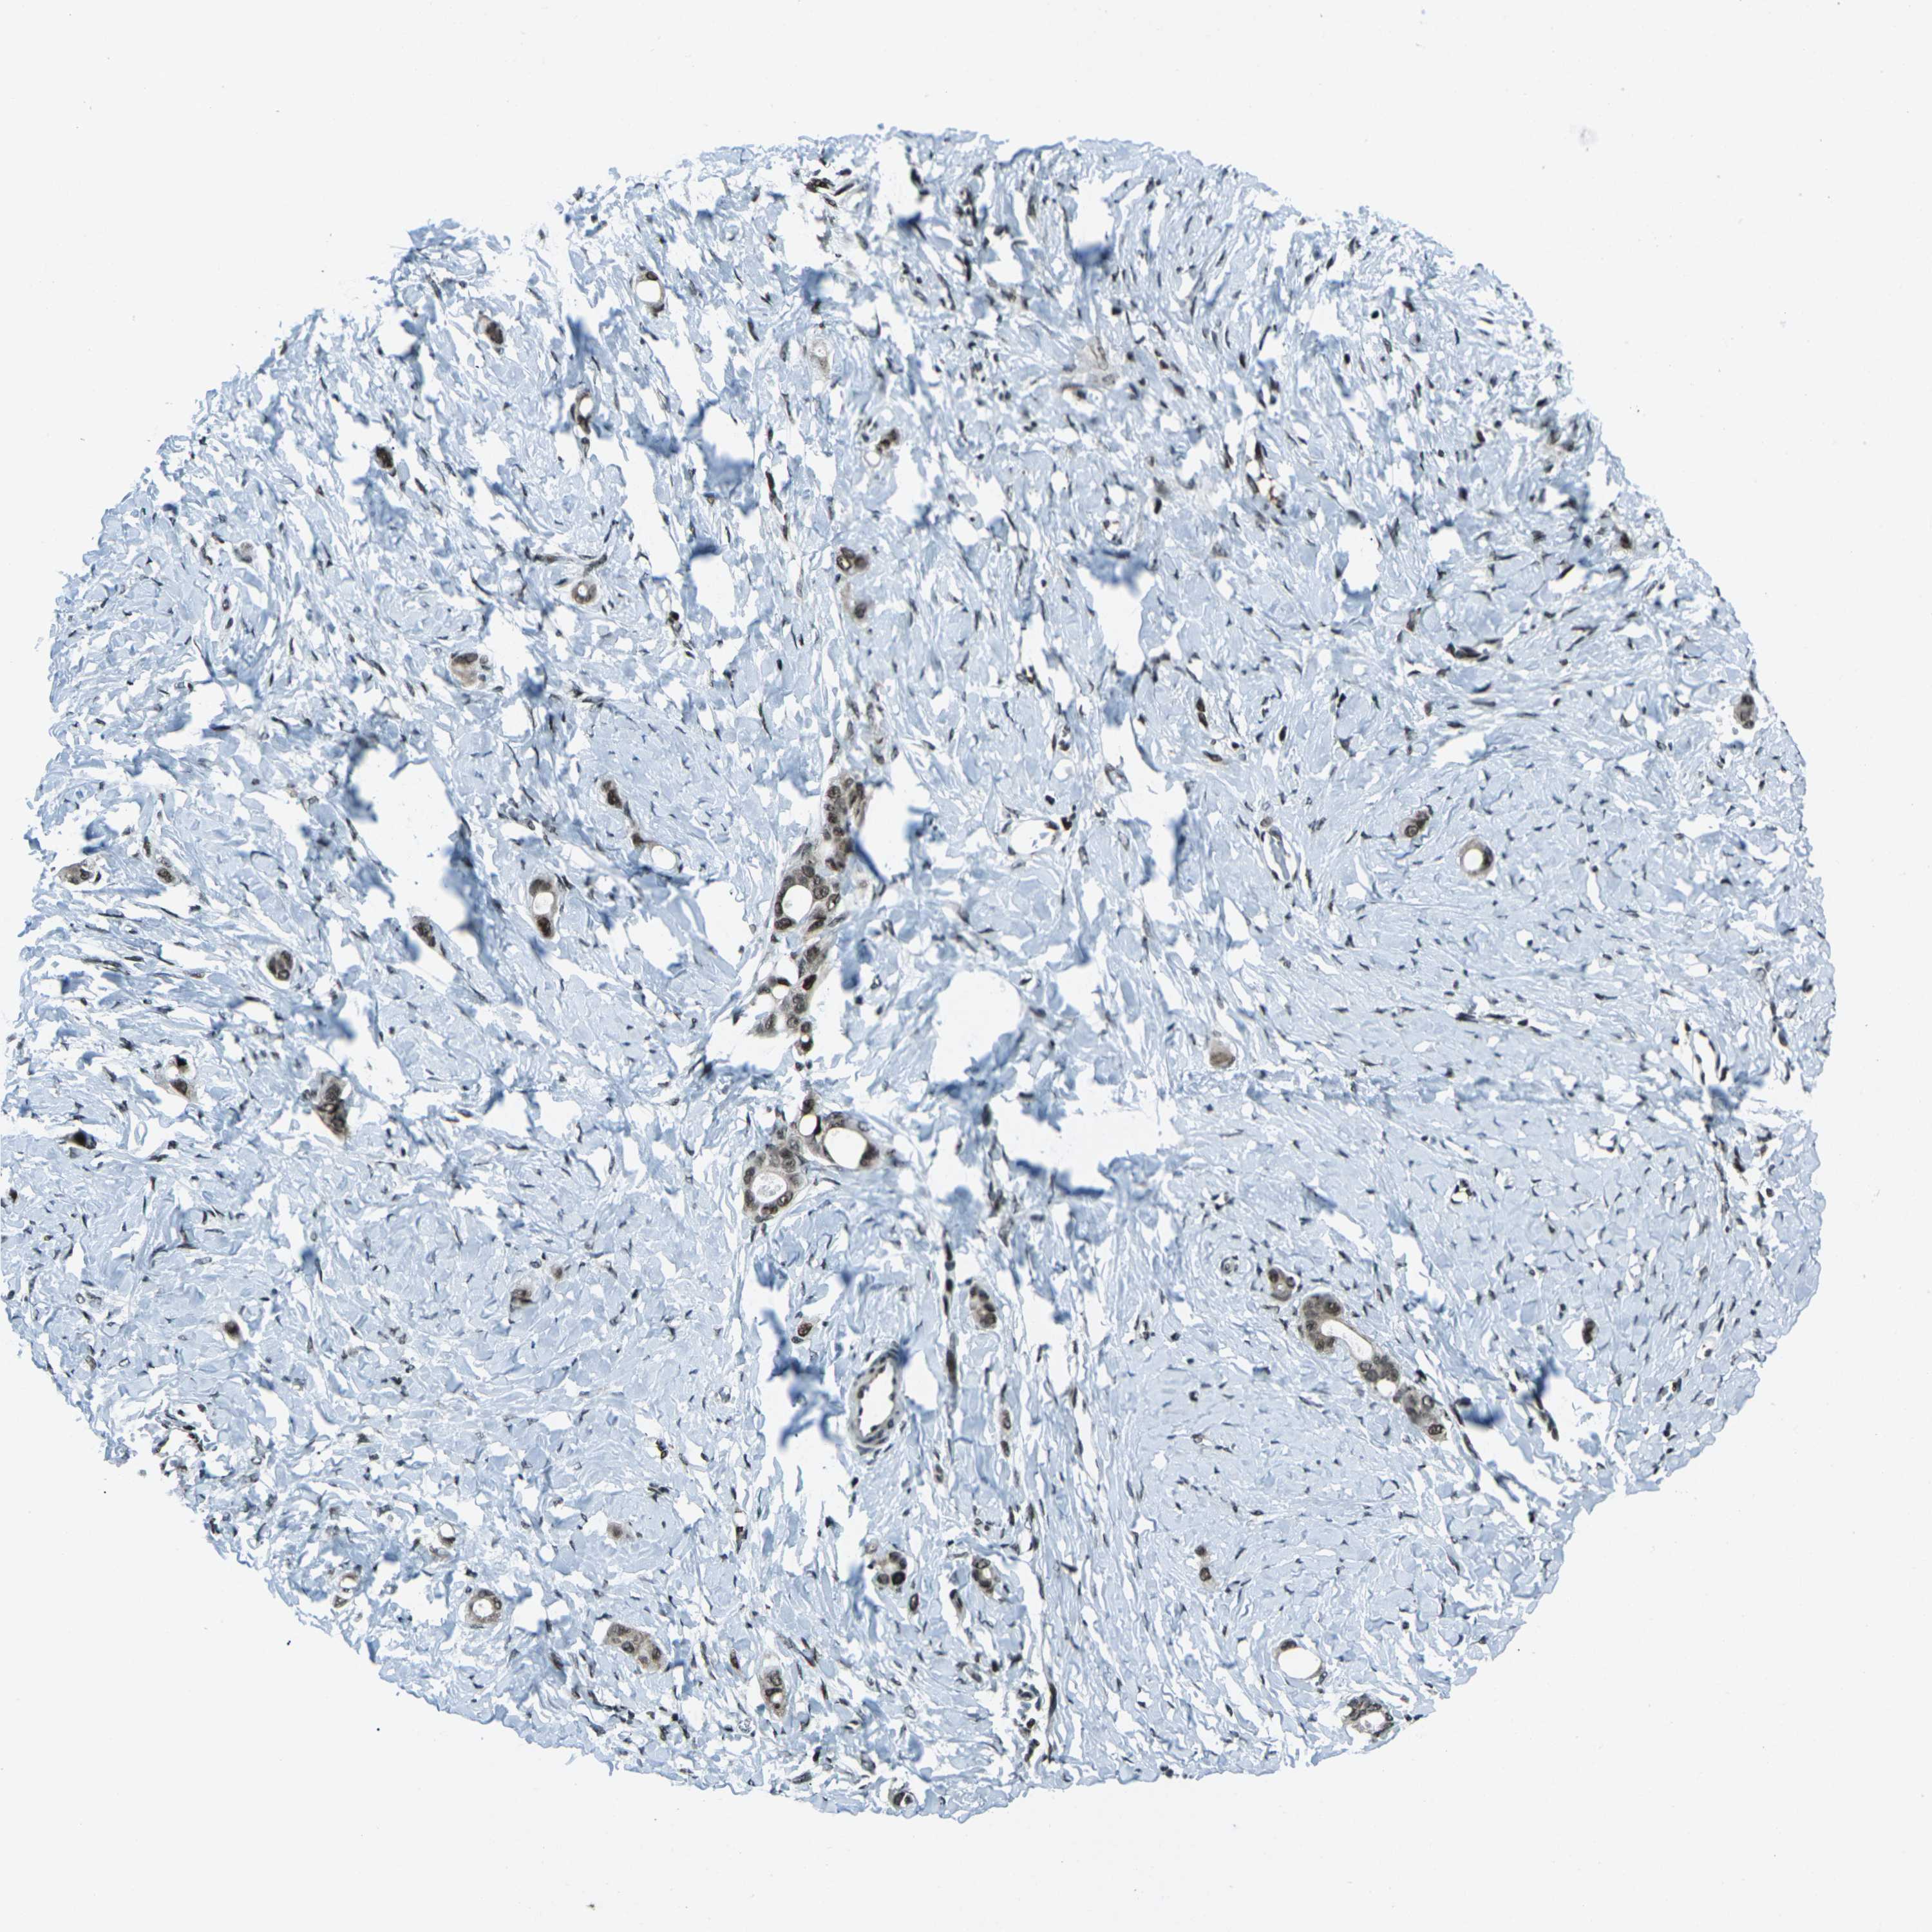

STOMACH CANCER - Protein expressioni

A mouse-over function shows sample information and annotation data. Click on an image to view it in a full screen mode. Samples can be filtered based on level of antibody staining by selecting one or several of the following categories: high, medium, low and not detected. The assay and annotation is described here.

Note that samples used for immunohistochemistry by the Human Protein Atlas do not correspond to samples in the TCGA dataset.

Antibody stainingi

Antibody staining in the annotated cell types in the current human tissue is reported as not detected, low, medium, or high, based on conventional immunohistochemistry profiling in selected tissues. This score is based on the combination of the staining intensity and fraction of stained cells.

Each image is clickable and will lead to virtual microscopy that enables deeper exploration of all samples and also displays staining intensity scores, fraction scores and subcellular localization as well as patient and tissue information for each sample.

Antibody CAB012272

Staining

High

Medium

Low

Not detected

Intensity

Strong

Moderate

Weak

Negative

Quantity

>75%

75%-25%

<25%

None

Location

Nuclear

Cytoplasmic/membranous

Cytoplasmic/membranous,nuclear

Adenocarcinoma, NOS

Adenocarcinoma, High grade